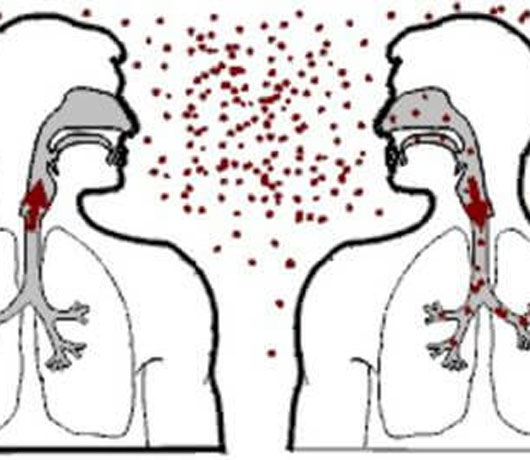

Khi mắc bệnh lao, trong cơ thể mỗi người có hàng triệu trực khuẩn lao, các vi khuẩn này theo đàm, nước bọt…bắn ra môi trường không khí. Theo ước tính, khi ho, khạc nhổ một bệnh nhân lao cho ra ngoài hơn 3000 vi khuẩn lao, khi hắt hơi con số này lên tới 1.000.000 vi khuẩn. Các vi khuẩn này bay lơ lửng trong môi trường không khí, người bình thường hít phải sẽ nhiễm bệnh. Vì vậy, lao là bệnh có khả năng lây nhiễm vô cùng cao, mặt khác, đối với những người có sức đề kháng yếu, hệ miễn dịch suy giảm, sẽ tạo điều kiện thuận lợi cho lao bùng phát, nhất là với những người đã điều trị lao, phổi bị tổn thương, cộng với các yếu tố khác tác động như sức khỏe, dinh dưỡng, môi trường…khiến lao tái phát lại là điều hoàn toàn dễ hiểu.

Người tiếp xúc với bệnh nhân lao,khả năng nhiễm lao cũng vô cùng cao. Lao là gánh nặng của gia đình và xã hội, nhưng chúng ta hoàn toàn có thể kiểm soát nó nếu hiểu và có phương pháp cụ thể.